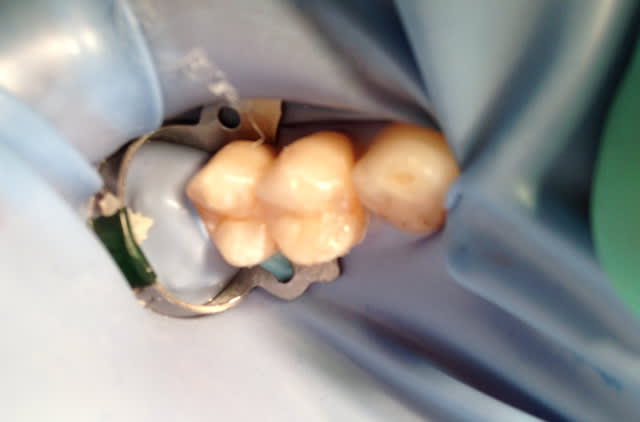

Aujourd'hui, j'en ai posé 2 autres (25 dévitalisée, 14 vivante); pas d'essayage (merci céramik), mise en place de la digue direct, collage puis retouches.

Désolé pour les photos pas terribles, le rendu final était pas trop mal, l'occlusion aussi.